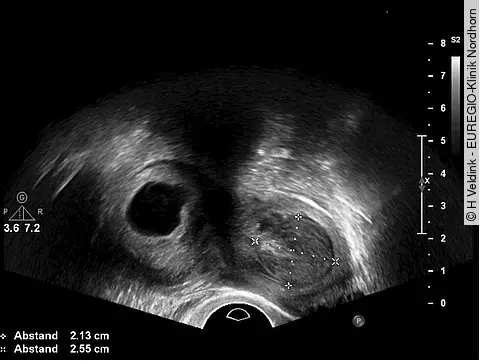

Dr. Hendrik Veldink, EUREGIO-Klinik Nordhorn

QuizAuflösung: Uterusanomalie im transvaginalen Ultraschall

Zu sehen ist ein Uterus bicornis mit einer echoleeren Formation im rechten Uterushorn, bei der es sich um eine Fruchthöhle einer Frühschwangerschaft handeln kann. Im linken Uterushorn ist eine mittelechodichte Formation im Uteruscavum zu sehen, die einem Hämatom entsprechen könnte.